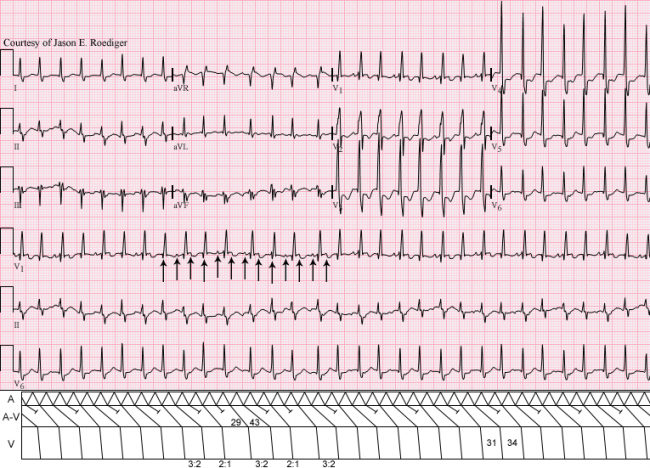

Patient data:  54-year old man who recently underwent a major cardiac procedure.  At first glance, this ECG may not appear to be particularly unique but a closer inspection reveals something unusual going on here.

HINT:  The telling clue can be found in lead II but you'll have to use calipers and think "outside-the-box".  3 days after this ECG, the patient reverted back to sinus rhythm but continued to display this one finding.  Good luck!